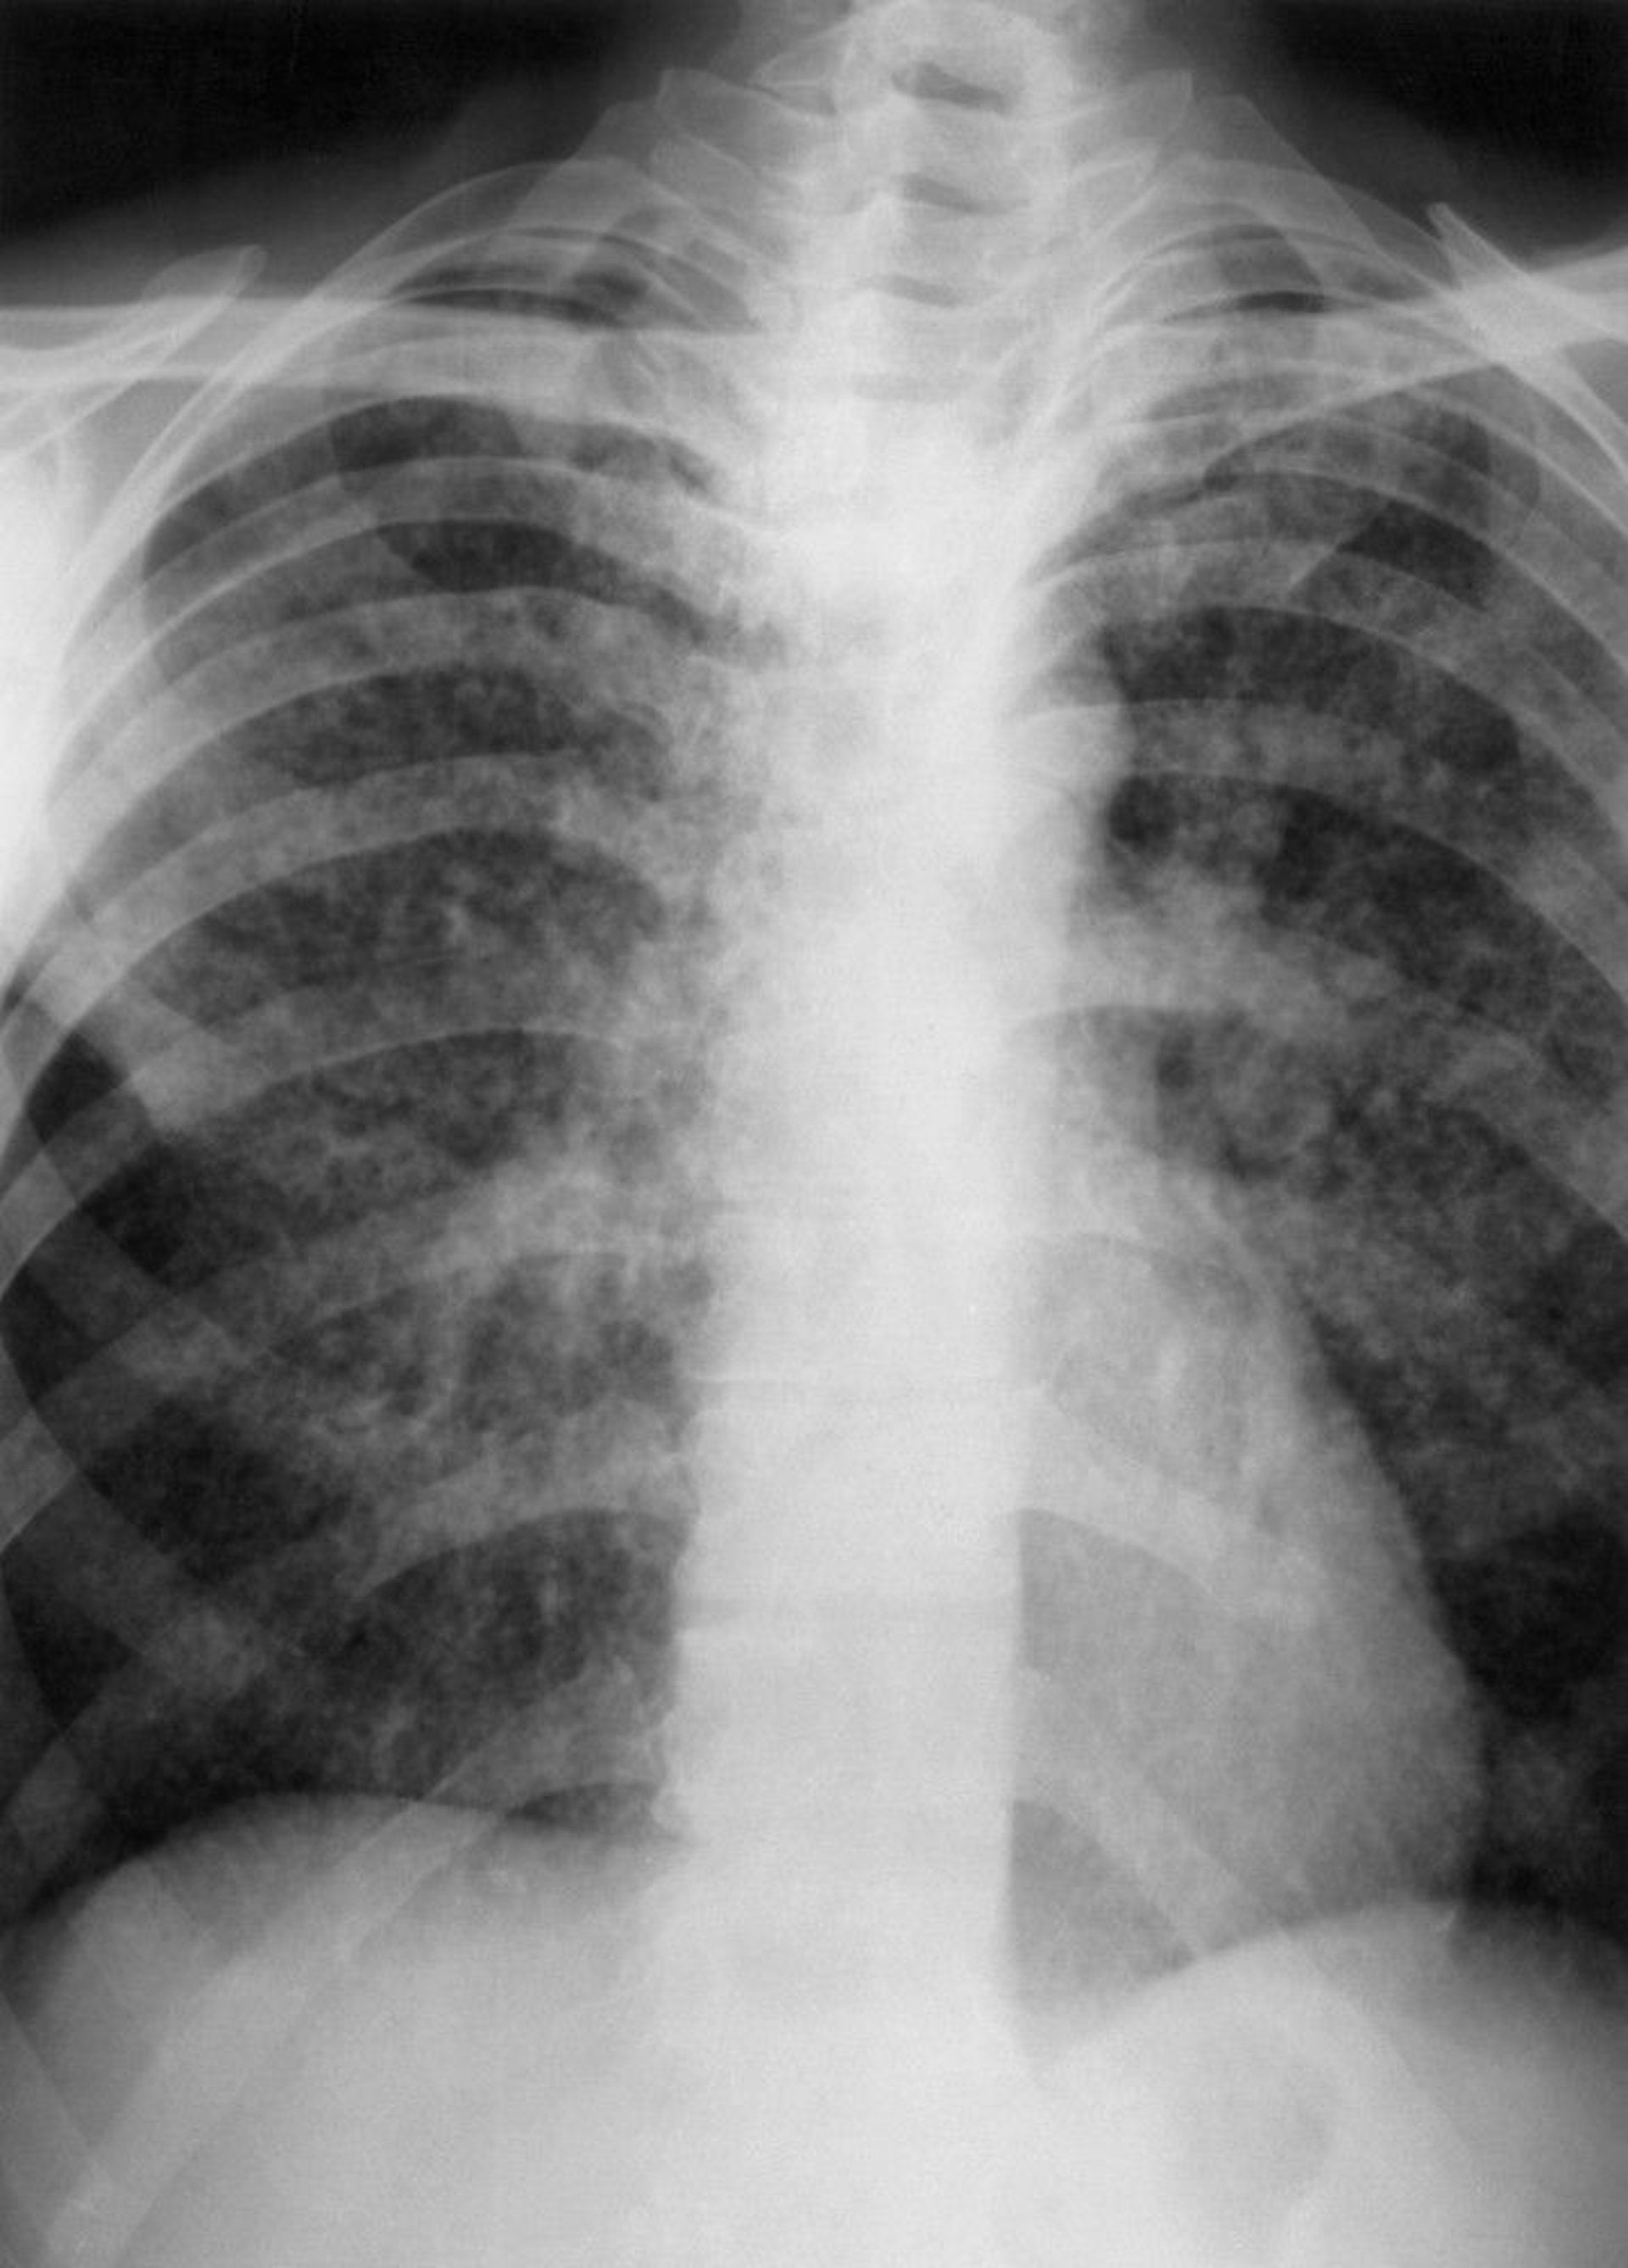

Miliary TB

This chest x-ray show findings suggesting miliary tuberculosis (TB), including almost innumerable, tiny (eg, 2- to 3-mm), interstitial nodules distributed through both lungs.